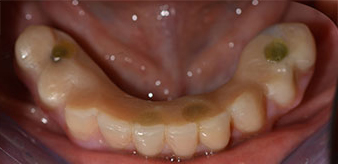

The impression and bite registration were then performed so that the dental technician could begin producing the provisional restoration immediately. This was then screwed in on the same day (Fig. 17 and 18).

Implants

Fig. 17

Fig. 18